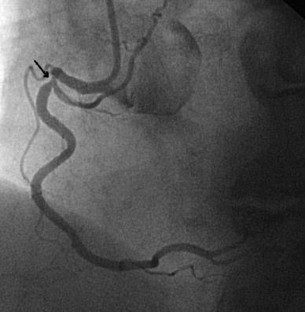

Fractional flow reserve (FFR) is a standardized and well-established method frequently used in clinical practice to evaluate the hemodynamic significance of epicardial coronary stenosis identified by coronary angiography. It is based on the change in the pressure gradient across the stenosis after the achievement of maximal hyperemia of the coronary circulation which is commonly induced by intravenous (IV) or intracoronary (IC) administration of adenosine. Here, we have described three cases of IC adenosine-induced ventricular arrhythmias during FFR measurement from our institution, and after literature review we found that all the cases of ventricular arrhythmias induced by adenosine during FFR measurement were observed where it was administered via IC route. Although a causal relationship between the use of IC adenosine during FFR measurement and the induction of ventricular arrhythmias is not yet established, we suggest using IV adenosine as the preferred route of administration until we better understand the incidence and mechanism underlying this phenomenon.

Raffaele P, Tullio N, Giuseppe G, et al. Adenosine-induced torsade de pointes complicating a fractional flow reserve measurement in a right coronary artery intermediate stenosis. Cardiovasc Revascularization Med. 2013;14:118–20.

Shah AH, Chan W, Seidelin PH. Ventricular fibrillation precipitated by intracoronary adenosine during fractional flow reserve assessment: a cautionary tale. Heart Lung Circ. 2015;11:e173–5.